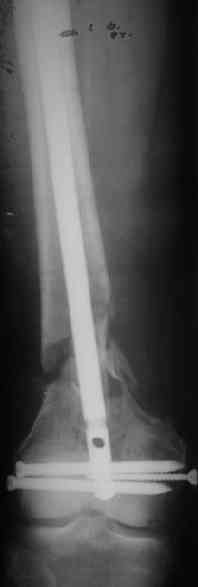

> Мужчина 60 лет, оперирован 2 месяца назад...

... Наверно, надо удалить эту пластинку и сделать реостеосинтез.

> Хочется гвоздем. Или лучше не гвоздем?

Я бы предпочел реостеосинтез "не гвоздем". Хотя в свежем случае это был бы штифт...

Есть подозрение, что мыщелки отрепонированы между собой неидеально, как-будто наружный завален кзади (угол открыт кпереди). Надо удалять все железо, репонировать открыто суставные поверхности и... Я бы выбрал LCP DF (LISS) на 9 отверстий (3-5 отверстий в зоне метафизарного перелома оставить

пустыми)...

Укорочение около 2 см. Движения в колене - 45

градусов.

Как быть с укорочением?... Надо ли что-то одномоментно делать по поводу контрактуры колена?